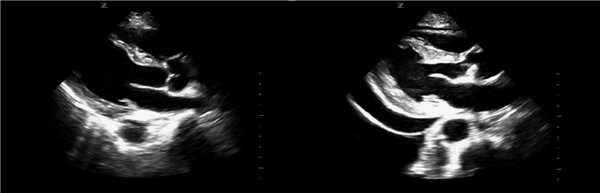

Эхокардиография

Эхокардиография является важным исследованием при диагностике ЛГ, так как помимо ориентировочного диагноза, позволяет зафиксировать первичные нарушения, вызвавшие ЛГ (ВПС с шунтированием, нарушение работы левых отделов сердца, возможные кардиальные осложнения).

2. признаки ЛГ: дилатация правых отделов сердца, клапана и ствола легочной артерии, аномальное движение и функция межжелудочковой перегородки, увеличение толщины стенок

правого желудочка, увеличение скорости регургитации на клапане легочной артерии, укорочение времени акцелерации выброса из ПЖ в ЛА.

Рис. Эхо-признаки умеренного гидроперикарда, тампонады сердца у больного в ситуации шока.